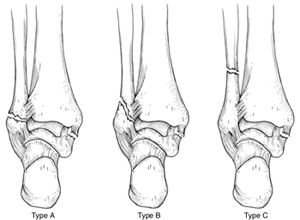

Different levels of lateral malleolus fractures

Reproduced with permission from Michelson JD: Ankle Fractures Resulting From Rotational Injuries J Am Acad Ortho Surg 2003;11:403-412.